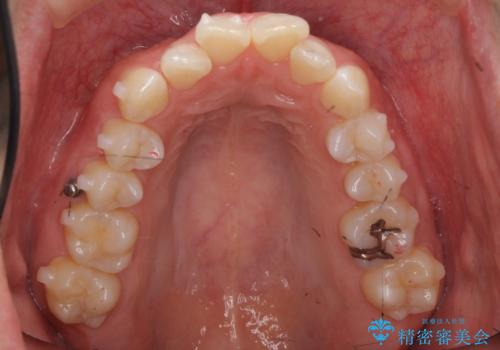

前歯をさげたい 歯を抜かずに マウスピース矯正で治したい

- 上の前歯が出ているとのことで来院。

歯を抜かずに、上の奥歯を後ろにさげつつ上の前歯を小さく少し削る処置を行い前歯の角度を修正しました。

右上下の奥歯もすれ違い咬合も、治療で改善しています。

下の前歯が生まれつき3本でしたので上下の正中は合わない仕上がりとなります。